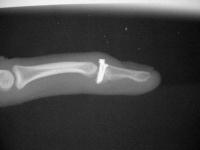

The injury:dorsal DIP fracture dislocation of the ring finger of a 16 year old male sports hopeful.

Unstable even in a well molded splint.